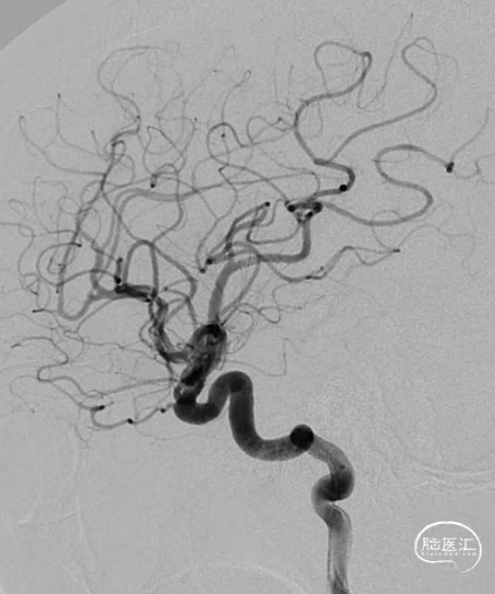

术前影像学检查

我院头颅CT平扫加CTA示。

造影示左侧大脑前A2近端闭塞。长鞘+5F 中间导管+18微导管+0.014inch微导丝。

前向血流恢复,局部残余重度狭窄。

血流无法维持,跟进中间导管。

加奇SacSpeed®球囊扩张导管到位后缓慢扩张。

释放2.5x20mm支架。

复查造影示前向血流维持良好。